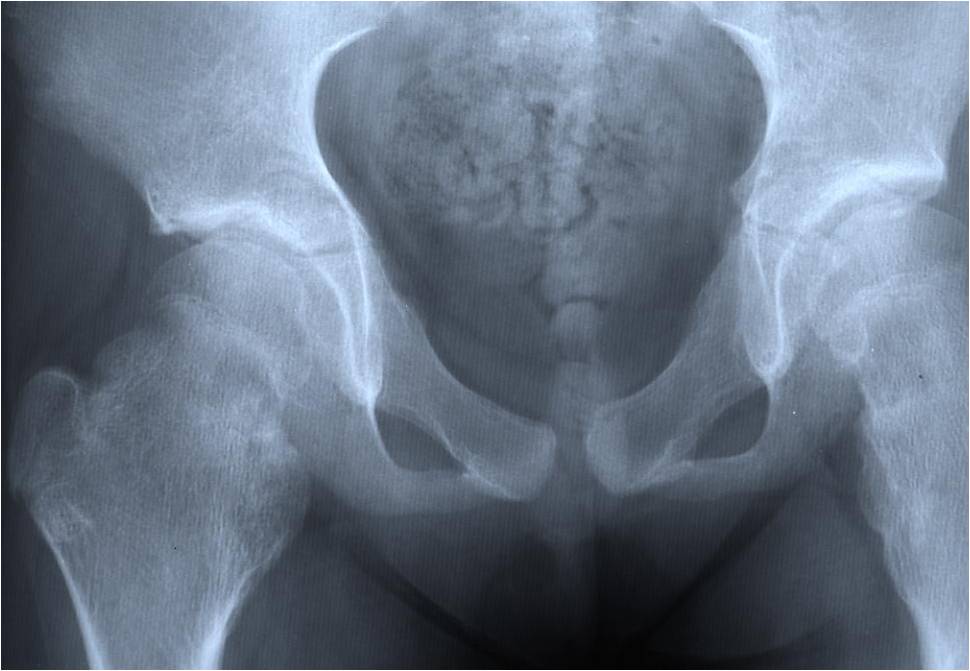

Plain X-ray: Secondary Chondrosarcoma of Proximal Femur

- Most common sites to undergo malignant change

- Scapula, pelvis, ribs, proximal femur